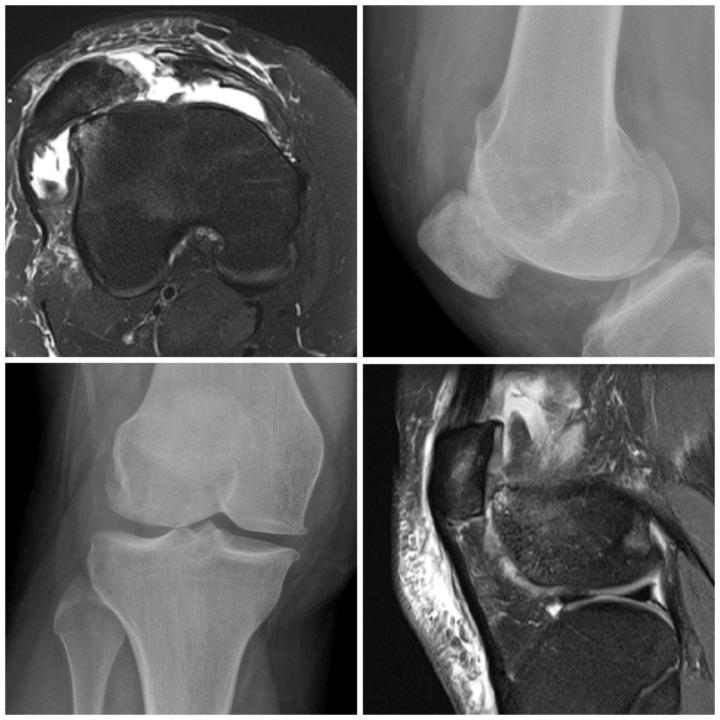

⚜️Osgood-Schlatter disease

🌟"Case Spotlight: Osgood-Schlatter Disease on X-ray and MRI⚜️ As a radiologist, I'd like to share a fascinating case of Osgood-Schlatter disease, a common cause of knee pain in adolescents. Clinical Presentation: - Pain and swelling below the kneecap - Typically affects active teenagers during growth spurts Imaging Findings: X-ray:🌟 - Soft tissue swelling and fragmentation of the tibial tuberosity MRI:🌟 - Edema and inflammation of the patellar tendon and surrounding soft tissues - Fragmentation and heterogeneity of the tibial tuberosity ⚜️Osgood-Schlatter disease is a self-limiting condition that resolves with maturity. However, imaging plays a crucial role in confirming the diagnosis and ruling out other potential causes of knee pain.